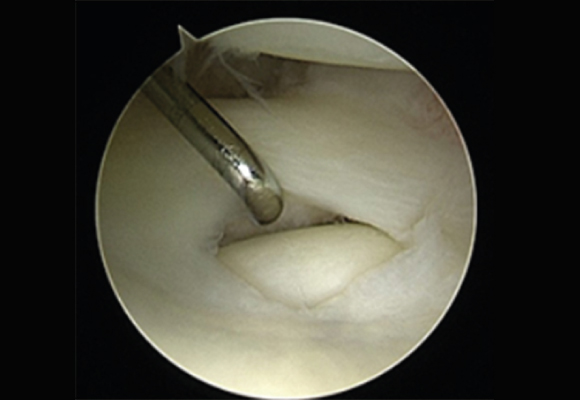

노화된 어깨의 관절낭을 절제해 간격을 넓혀주는 수술 시행

ㆍ환자의 동의를 받은 자료이며, 이미지 사진은 실물과 다를 수 있습니다. (16.09.30)